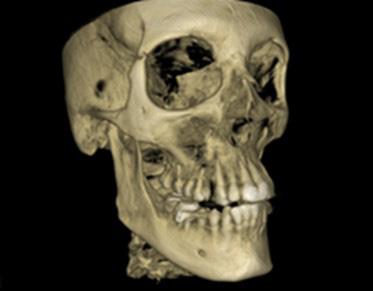

Lateral Cephalometric radiogram and tracing revealed robust lower airway (18.0/15mm), CVMS 6, maxilla and mandible are prognathic (SNA - 93° and SNB - 84°), Class II skeletal (ANB –9.0 mm, Witts – 9.0 mm). The patient was hyperdivergent (NS/ GoM – 30°, ALFH - 83 mm!!), protrusive maxillary incisors (U1/ SN – 117.0°), mandibular incisors were within the norm (L1/GoM 95.0°) and Harvold Δ was 30 mm. The soft tissue profile (lips) was convex (Figure 5-C, D).

FIG. 5C: Pre-treatment, Cephalometric radiogram

FIG. 5D: Pre-treatment,Cephalometric tracing